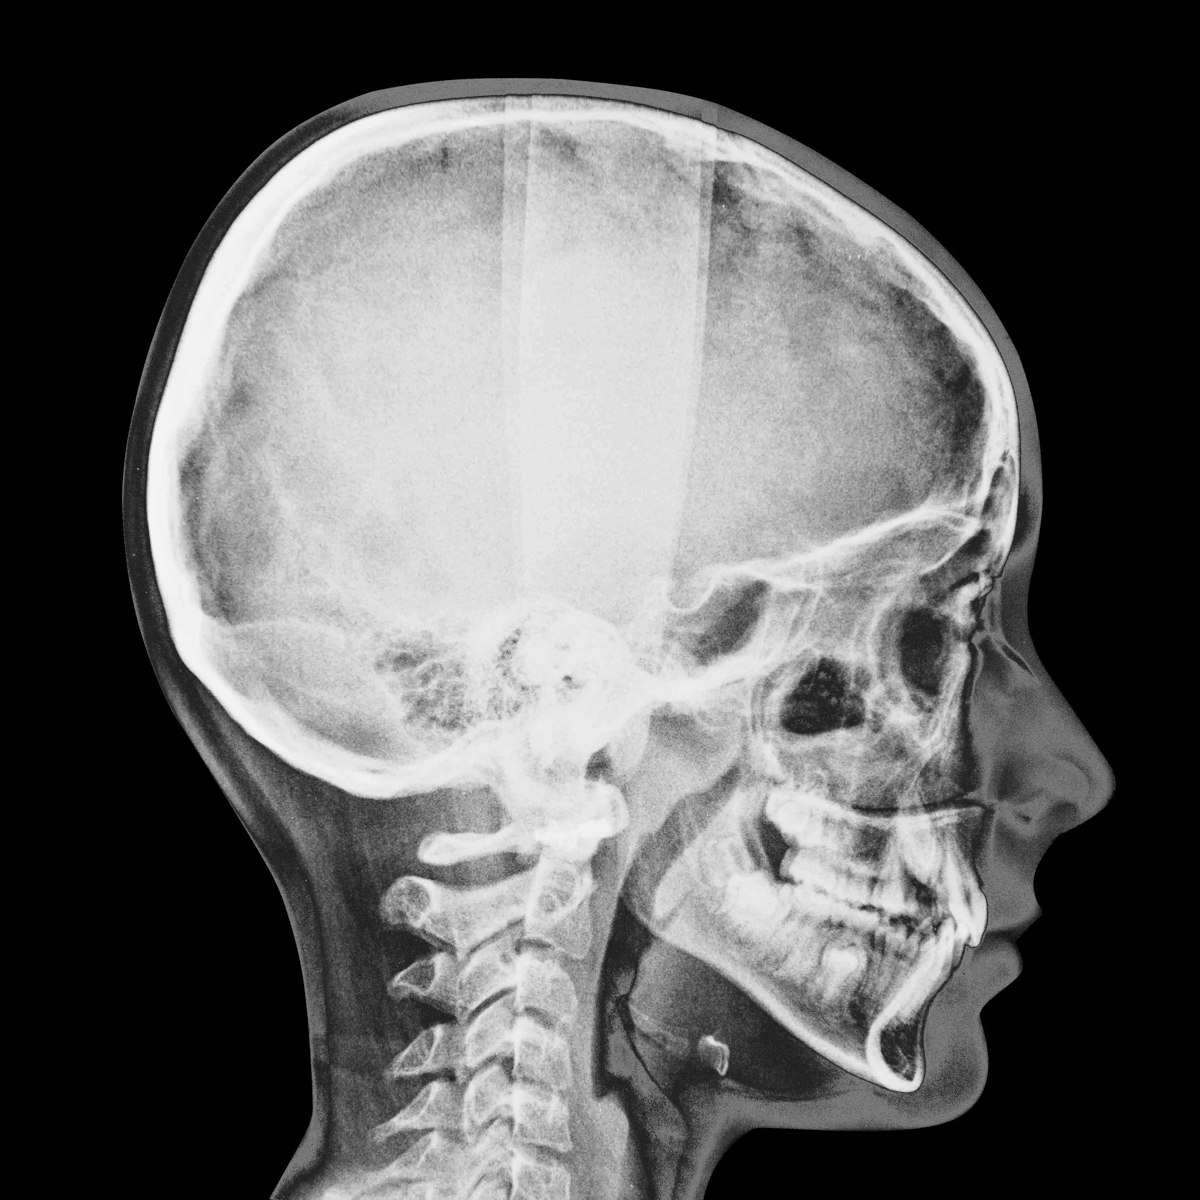

SURFACES SENSIBLES — À la frontière de l'autoportrait, "Surfaces sensibles" retranscrit une partie de ma réalité et brouille les limites entre l'intime anatomique et l'émotionnel.

La science produit les images les plus concrètes et les plus neutres pour illustrer les affects. Pourtant, par leur froideur et leur distance, elles sont les moins aptes à témoigner des émotions. Chaque radiographie, scanner, IRM correspond à une douleur ou à un mal-être spécifique.

Depuis peu, ces images ne sont plus seulement des réminiscences de douleurs passées, mais également des matériaux bruts inspirants pour ma pratique photographique. À partir des radios originelles, j'ai utilisé plusieurs techniques telles que la superposition et le tirage argentique dans le but de me rapprocher d'une perception alternative de ce corps irradié.